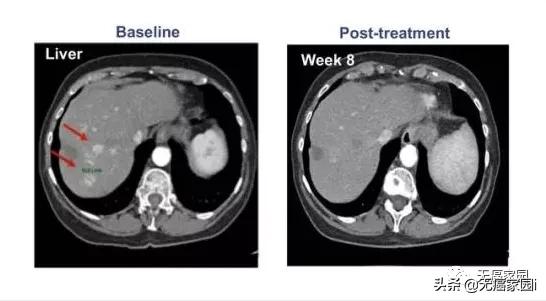

其中1例晚期肝癌患者接受了瘤内注射CAR-T治疗,治疗后肝脏病灶代谢基本消失。

CAR-T细胞 注射60天后 ,虽然2个肺部结节的尺寸没有显著的改变,但在 第10天时肝脏肿瘤病变(1.2×1.3cm)显著收缩 , 注射GPC3-7×19 CAR-T细胞第32天后则完全消失。

患者没有任何毒性作用,并且根据 CT 上的标准实体瘤反应评估标准 (RECIST) 1.1 版进行了分期评估,显示部分缓解 (PR)。